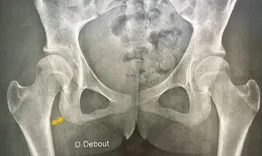

Live clinic - FAI, dysplasia, extra-articular pathology

What makes total hip arthroplasty in young patients so specific? From anatomical challenges to sports recovery and long-term outcomes, this session explores key considerations, surgical strategies, and patient expectations in this demanding population.